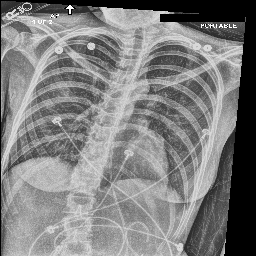

[Uncaptioned image] cardiomegaly is moderate. bibasilar atelectasis is mild. there is no pneumothorax. a lower cervical spinal fusion is partially visualized. healed right rib fractures are incidentally noted. ap portable upright view of the chest. there is no focal consolidation, effusion, or pneumothorax. the cardiomediastinal silhouette is normal. imaged osseous structures are intact. pa and lateral views of the chest. there is mild enlargement of the cardiac silhouette. there is no pleural effusion or pneumothorax. there is no acute osseous abnormalities.

[Uncaptioned image] as compared to the previous radiograph, the monitoring and support devices are unchanged. unchanged bilateral pleural effusions, with a tendency to increase, and resultant areas of atelectasis. the air collection in the bilateral soft tissues is slightly decreased. unchanged right picc line. no definite evidence of pneumothorax. as compared to the previous radiograph, the patient has received a nasogastric tube. the course of the tube is unremarkable, the tip of the tube projects over the middle parts of the stomach. there is no evidence of complication, notably no pneumothorax. the other monitoring and support devices are constant. constant appearance of the cardiac silhouette and of the lung parenchyma. as compared to the previous radiograph, there is no relevant change. tracheostomy tube is in place. there is a layering pleural effusions. NAME bilateral pleural effusion and compressive atelectasis at the right base. there is no pneumothorax.

[Uncaptioned image] the course of the dobbhoff feeding catheter is unremarkable, and its tip is seen projecting over the stomach. there is no evidence of complications, specifically no pneumothorax. as compared to the prior radiograph dated DATE, there has been no other significant interval change. ap portable upright view of the chest. overlying ekg leads are present. there is no focal consolidation, effusion, or pneumothorax. the cardiomediastinal silhouette is normal. imaged osseous structures are intact. as compared to the previous radiograph, there is no relevant change. the endotracheal tube terminates approximately 3 cm above the NAME. the endotracheal tube extends into the stomach. there is no evidence of complications, notably no pneumothorax. there is no pleural effusion or pneumothorax.

[Uncaptioned image] interval placement of a left basilar pigtail chest tube with improving aeration in the left mid to lower lung and near complete resolution of the pleural effusion. there are residual patchy opacities within the left mid and lower lung as well as at the right base favoring resolving atelectasis. no pneumothorax is appreciated on this semi upright study. heart remains stably enlarged. mediastinal contours are stably widened, although this NAME be related to portable technique and positioning. this can be better evaluated on followup imaging. no pulmonary edema. as compared to the previous radiograph, the patient has been extubated. the nasogastric tube is in unchanged position. the lung volumes remain low. moderate cardiomegaly with minimal fluid overload but no overt pulmonary edema. no larger pleural effusions. no pneumonia. ap upright and lateral views of the chest. there is moderate cardiomegaly. there is no pleural effusion or pneumothorax. there is no acute osseous abnormalities.

Table 4: Sample images along with ground truth and generated reports. Note that upper case tokens are results of anonymization.

Table 4 demonstrates the qualitative results of our full model. In general, our models are able to generate descriptions that align with the logical flow of reports written by radiologists, which start from general information (such as views, previous comparison), positive, then negative findings, with the order of lung, heart, pleura, and others. TieNet also generates report descriptions with such logical flow but in slightly different orders. For the negative findings cases, both our model and TieNet do well on generating reasonable descriptions without significant errors. Regarding the cases with positive findings, TieNet and our full model both cannot identify all radiological findings. Our full model is able to identify the major finding in each demonstrated case. For example, cardiomegaly in the first case, pleural effusion, and atelectasis in the second case.

A formerly practicing clinician co-author reviewed a larger subset of our generated reports manually. They drew several conclusions. First, our full model tends to generate sentences related to pleural effusion, atelectasis, and cardiomegaly correctly—which is aligned with the clinical finding scores in Table 3. TieNet instead misses some positive findings in such cases. Second, there are significant issues in all generated reports, regardless of the source model, which include the description of supportive lines and tubes, as well as lung lesions. For example, TieNet is prone to generate nasogastric tube mentions while our model tends to mention tracheostomy or endotracheal tube, and yet both models have difficulty identifying some specific lines such as chest tube or PICC line. Similarly, both systems do not generate the sentence with positive lung parenchymal findings correctly.

From this (small) sample, we are unable to draw a conclusion whether our model or TieNet truly outperforms the other since both present with significant issues and each has strengths the other lacks. Critically, neither of them can describe the majority of the findings in the chest radiograph well, especially for positive cases, even if the quantitative metrics demonstrate the reasonable performance of the models. This illustrates that significant progress is still needed in this domain, perhaps building on the directions we explore here before these techniques could be deployed in a clinical environment.